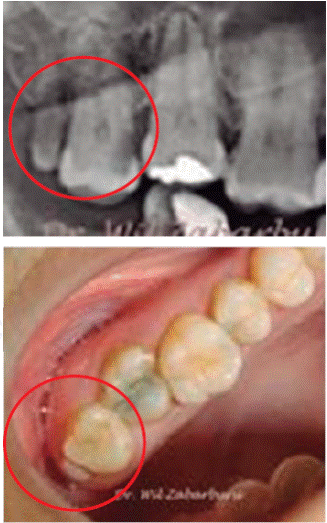

In some instances fourth molars fuse to third molars, and appear as a tubercle appended to its crown in the distal-lingual area, it is then called distomolar tubercle, it can even be appended to the third molar roots such as the palatine root in the case described by Gay-Escoda, Berini, Duarte and Azevedo14,15(Figure 6).

Duarte reported a case of an African American, 47 year old patient, with x-ray evidence of a radiopaque shape with characteristics of cementoblast or fourth molar; exploration clearly stated an inverted distomolar, fused to the palatal root of the third molar, additionally compromising the root canal (Figure 16).15